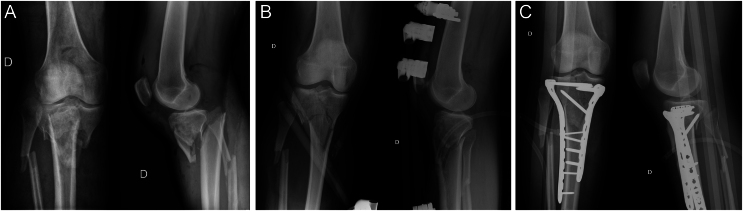

胫骨平台切开复位和固定后骨折相关感染(FRI)是一种常见的并发症,可导致灾难性的后遗症和巨大的经济成本,因此预防至关重要。根据患者相关因素、损伤相关因素和管理相关因素对危险因素进行分类是很有用的。与患者相关的因素,如吸烟,有大量证据表明它们与FRI有关,糖尿病和肥胖可能相关,但证据有些矛盾。然而,戒烟和多学科治疗对于预防FRI至关重要。损伤相关因素,如高能骨折和急性筋膜间室综合征,有令人信服的证据表明它们与FRI有关,必须承认它们是固有因素。虽然骨折暴露与感染有关,但尚未证实开放性骨折与胫骨平台骨折的FRI直接相关。同样,早期抗生素预防和手术清创是强制性的。至于治疗相关因素,手术时间的增加是FRI发生的重要预测因素。有关手术入路和钢板数量的证据显示FRI患病率呈上升趋势。对于外固定架的安装和拆卸,针板重叠尚未被确认或排除为危险因素。

Fracture-related infection (FRI) after tibial plateau open reduction and fixation is a common complication that leads to catastrophic sequelae and substantial economic costs, making prevention paramount. To facilitate an appropriate approach, it is useful to classify risk factors based on patient-related factors, injury-related factors, and management-related factors. Patient-related factors like smoking have a great amount of evidence establishing their relation with FRI. Diabetes and obesity might be associated, but evidence is somewhat conflicting. Nevertheless, smoking cessation and a multidisciplinary approach for these pathologies are essential to prevent FRI. Injury-related factors like high-energy fractures and acute compartment syndrome have compelling evidence relating them to FRI and must be acknowledged as inherent factors. While the exposure of the fracture has been associated with infection, open fractures are yet to be confirmed as directly related to FRI in tibial plateau fractures. Likewise, early antibiotic prophylaxis and surgical debridement are mandatory. As for management-related factors, increased surgical time emerges as a strong predictor for FRI. Evidence regarding the number of surgical approaches and plates shows a trend toward an increase in FRI prevalence. With respect to external fixator installation and removal, pin-plate overlapping is yet to be confirmed or ruled out as risk factors.